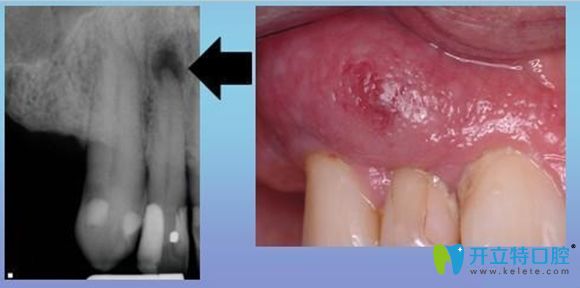

牙齦瘺管癥狀示意圖

它的臨床癥狀多表現(xiàn)為,患牙根部位置會(huì)先出現(xiàn)一個(gè)腫包,然后這個(gè)包會(huì)逐漸變大,并伴隨著分泌物溢出。

是因?yàn)榧毙愿庵苎装Y形成膿腫,膿液引流不暢,往外排出導(dǎo)致的,也可以說是根尖周炎癥常見的一種排膿途徑。